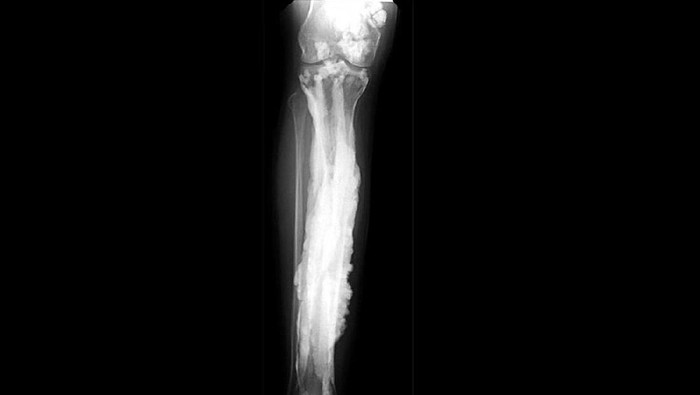

Karena ciri khasnya melorheostosis sering disebut juga sebagai penyakit tulang lilin. Menurut studi terbaru yang dipublikasi di jurnal Nature Communications hanya ada 400 kasus penyakit tulang lilin yang pernah tercatat.

Meski disebut penyakit tulang lilin bukan berarti tulang seorang pasien jadi lemah. Sebaliknya karena ada pertumbuhan abnormal tulang malah jadi menebal dan keras. Hal ini dapat menyebabkan keluhan seperti rasa nyeri, sulit bergerak, hingga kecacatan.